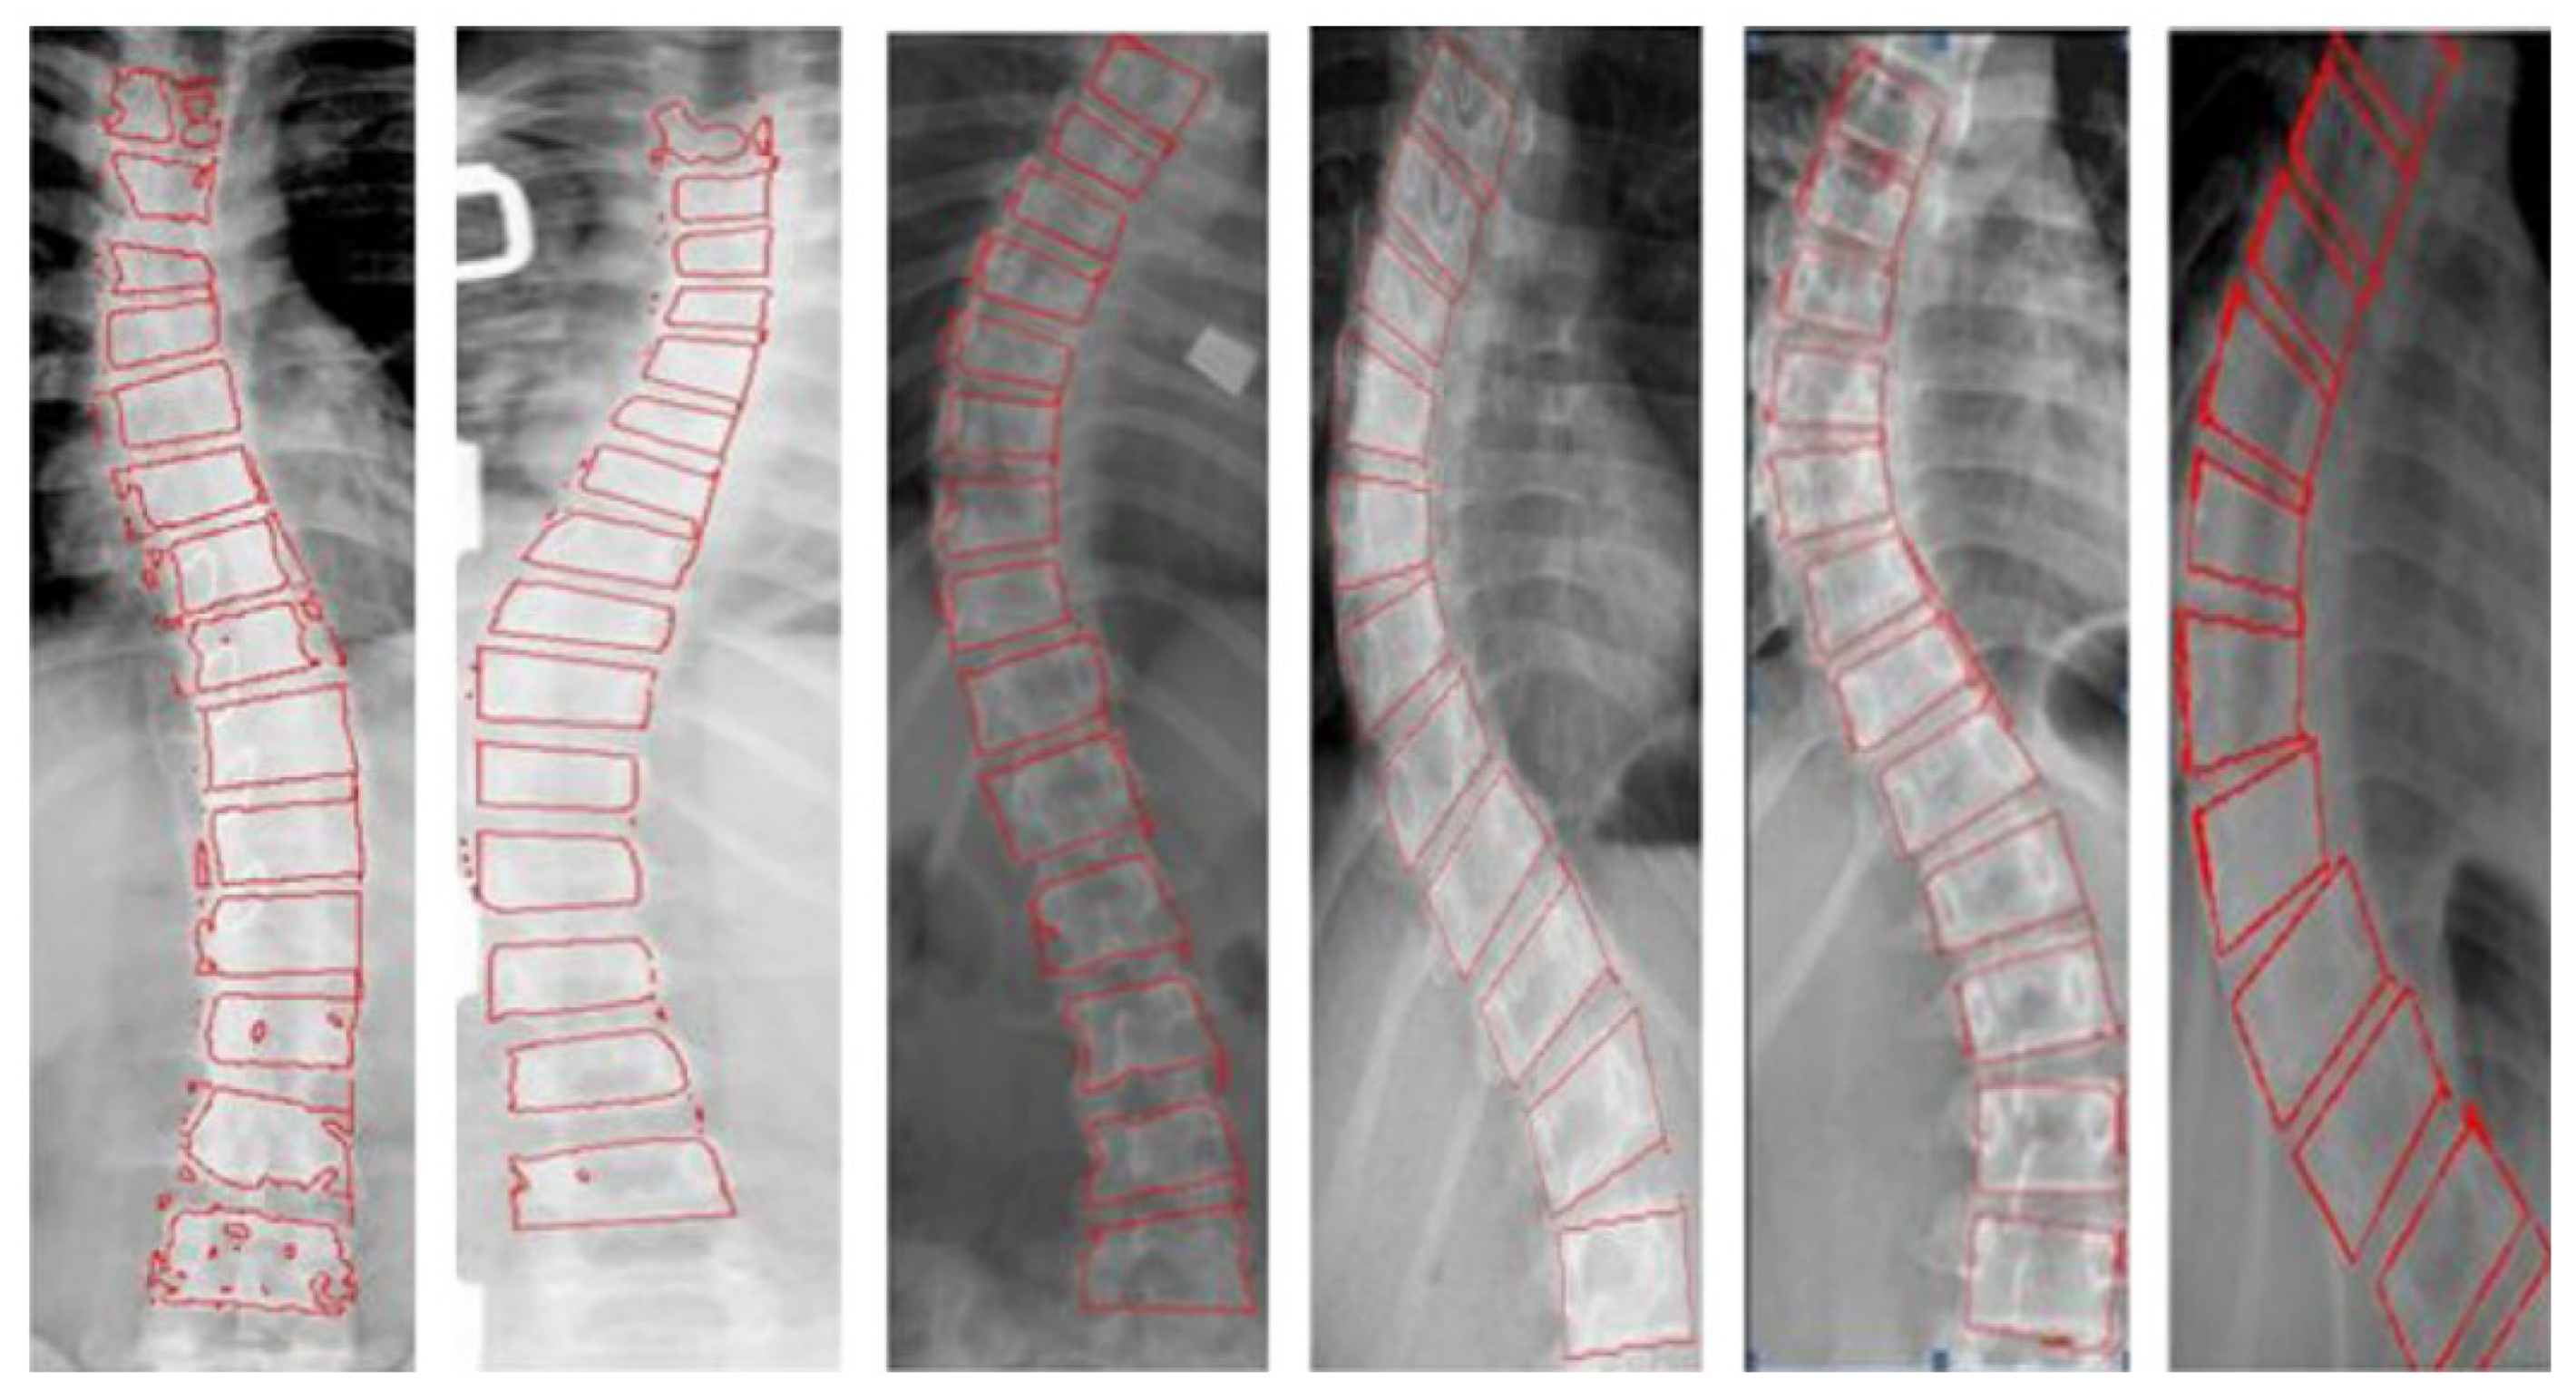

4.2.1. Segment the Vertebral Body to Measure the Cobb Angle

4.2.2. Locate the Landmark of the Spine to Measure the Cobb Angle